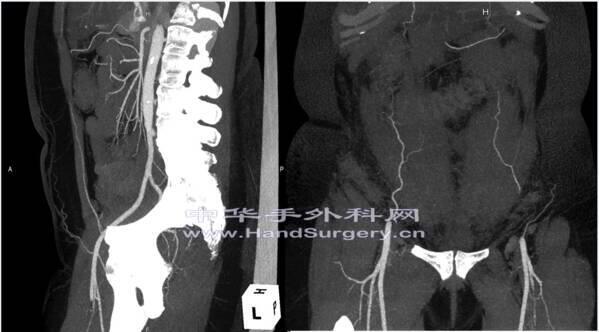

怎么能做出这么清晰的腹部下动脉造影图片呢